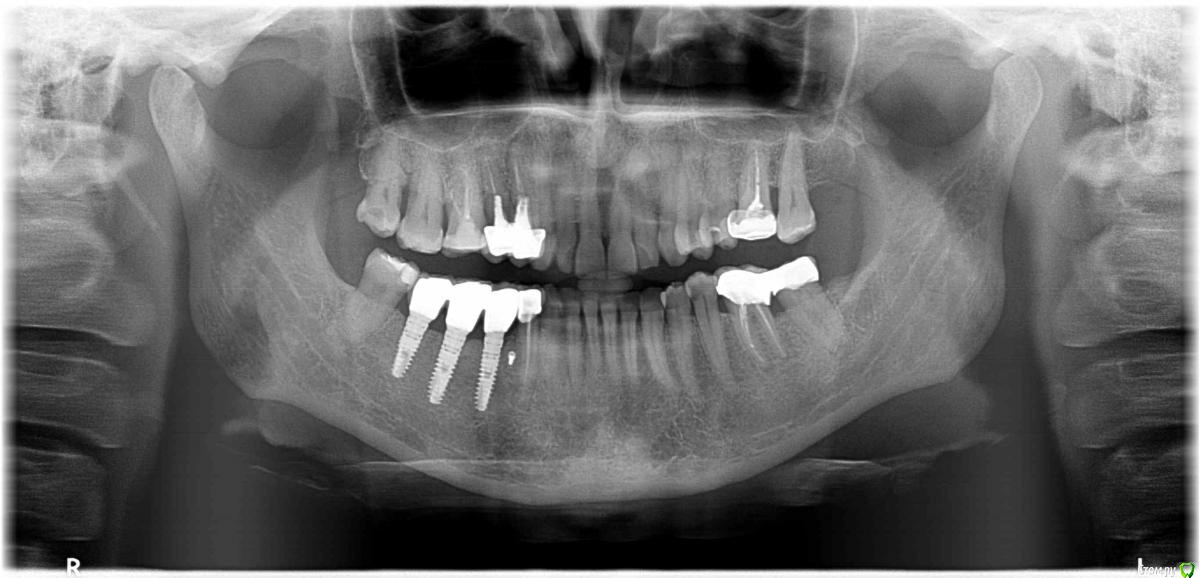

Анжела 66 Опубликовано 8 апреля, 2016 Поделиться Опубликовано 8 апреля, 2016 Добрый день, уважаемые доктора. Хотелось бы узнать ваше мнение о шансах верхней 4-ки и 5-ки.Первый, панорамный снимок, был сделан за день до появления флюса над верхней 4-кой .Второй, прицельный снимок, был сделан уже через пару дней после вскрытия флюса и наложения антибактериальной мази.Из-за небольшой подвижности резекцию корня не делали. Так же удаление штифтов не планируют. Был проведен только закрытый кюретаж, многократное наложение антибактериальной мази и длительное ( более месяца) полоскание Хлоргексамедом. Затем еще профессиональная чистка зубов.В настоящий момент оба зуба пока в спокойном состоянии. Но надолго ли? Что можно было бы предпринять еще?Заранее благодарю за ваши ответы Ссылка на комментарий

Ker Опубликовано 9 апреля, 2016 Поделиться Опубликовано 9 апреля, 2016 Добрый день, уважаемые доктора. В настоящий момент оба зуба пока в спокойном состоянии. Но надолго ли? Что можно было бы предпринять еще? Здравствуйте, увы, ненадолго. В канале(ах) четвертого зуба ложный ход и перфорация. Плюс уже приличная убыль костной ткани. Перелечить вряд-ли возможно (и особого смысла не имеет), удаление и имплантация, имхо. Ссылка на комментарий

St. Опубликовано 9 апреля, 2016 Поделиться Опубликовано 9 апреля, 2016 В случае удаление, оба зуба идут на удаление? Нет никакой возможности какой нибудь из двух зубов спасти?4 на удаление, 5 - шансы есть, если там тоже нет перфорации от штифта. Ссылка на комментарий

ЕленаВалерьевна Опубликовано 10 апреля, 2016 Поделиться Опубликовано 10 апреля, 2016 (изменено) Спасибо, за ответ.Еще один маленький вопрос:видите ли вы на 5-ке внизу глубокий кариес?Дело в том, что зуб совершенно не беспокоит. Возможно ли такое?на нижней 5-ке да, есть. конечно возможно. Изменено 10 апреля, 2016 пользователем ЕленаВалерьевна Ссылка на комментарий